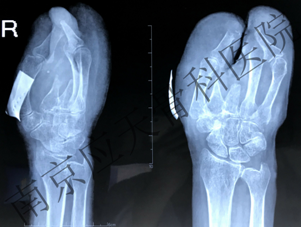

术前:

患者安徽滁州居民,于1999年因外伤致右手机器绞伤,在当地医院就诊,行手术治疗,术后伤口愈合可,后于2019年9月底右手拇指残端皮肤破损,就诊当地医院,予以保守治疗,效果不佳,为进一步治疗,来我院就诊。

患者入院后,管床医生根据病史及相关检查,明确诊断,制定手术方案。手术顺利完成,术后予以对症治疗,患者伤口愈合。